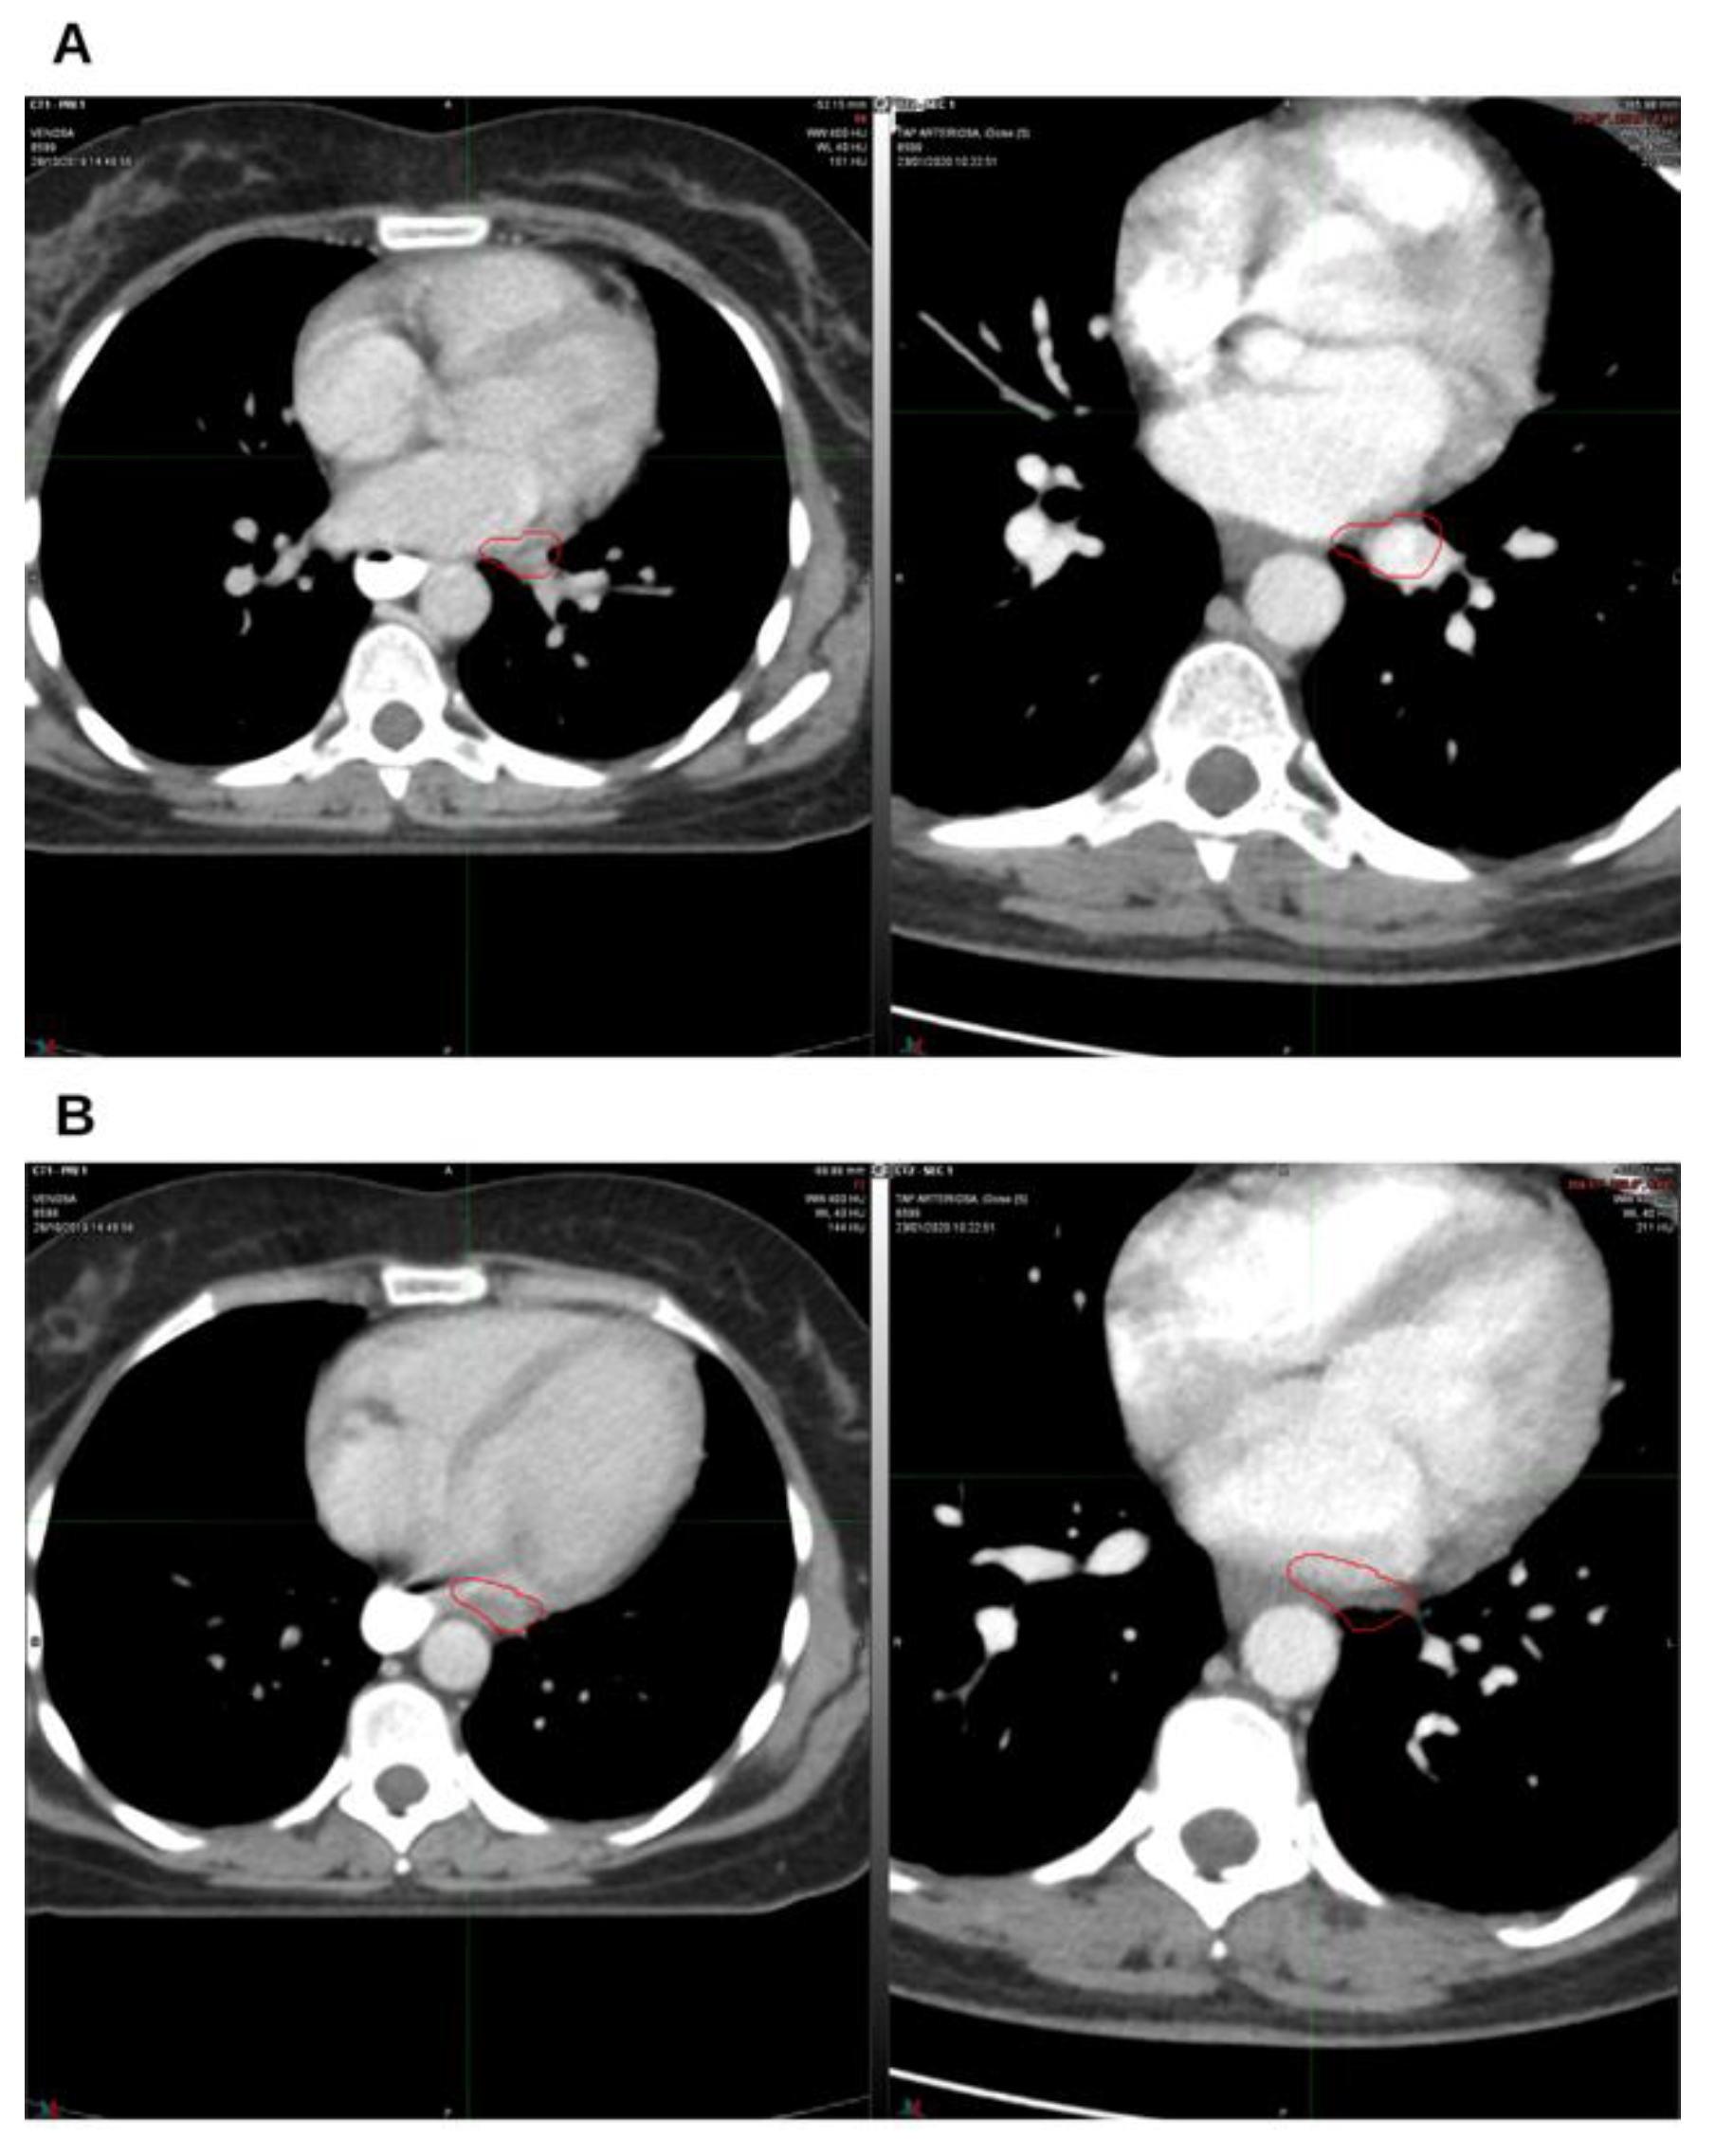

Background and Clinical Significance: Breast cancer is the most frequent malignancy in women. Advanced metastatic breast cancer is considered a treatable but incurable condition, with a median overall survival of only 2-3 years. Among its subtypes, triple-negative breast cancer (TNBC) accounts for a high proportion of breast cancer–related deaths. It is characterized by an aggressive clinical course, early recurrence, and a strong propensity for visceral and brain metastases. Case Presentation :We report the case of a Caucasian woman who, two years after being initially diagnosed and treated for TNBC, developed disease relapse with lung and mediastinal lymph node metastases. The patient received three months of chemotherapy combined with an adjuvant integrative protocol consisting of melatonin, cannabidiol, and oxygen–ozone therapy. This combined approach led to the complete disappearance of the lung nodules. Subsequently, stereotactic radiotherapy was performed and, in association with the ongoing integrative treatment, resulted in a significant reduction of mediastinal adenopathy. Introduction of immunotherapy, supported continuously by the same adjuvant strategy, achieved a complete and durable remission. Strikingly, the patient remained disease-free five years after the diagnosis of lung and mediastinal metastases. Conclusions: This clinical case highlights the potential benefit of using melatonin, cannabidiol, and oxygen–ozone therapy as part of an integrative approach in patients with aggressive metastatic TNBC. While it is not possible to establish causality from a single case, the sustained remission observed suggests that such unconventional adjuvant strategies could play a supportive role in enhancing the efficacy of standard oncologic therapies.